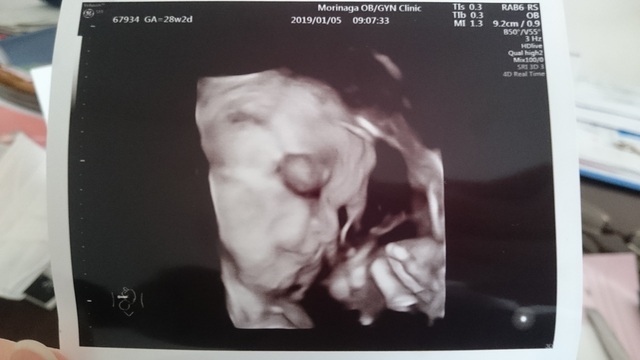

29週5日(29w5d・女の子)|まみつやこ さん(29歳)

エコー写真撮影時のエピソード:

今までは脚や手で顔を隠してばかりいたが、バッチリ顔が見えた初めての3D写真だった。年末の検診だったので、この写真を見ながらお正月に「どっちに似てるか?」「鼻は夫?」「輪郭は妻?」「二重かなぁ~」「だいぶ赤ちゃんらしい顔になってきた」と、親戚と話すのが楽しかった。